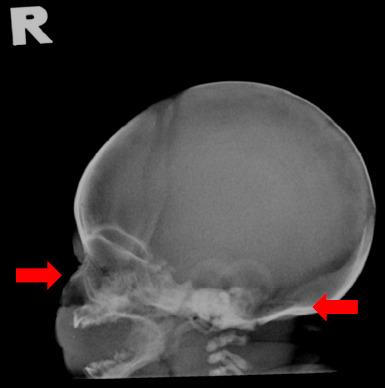

基层医疗环境中软骨发育不全的产前诊断——识别软指标:一例报告

Prenatal diagnosis of achondroplasia in primary care settings - Recognising the soft markers: A case report.

Achondroplasia, a genetic disorder causing limb shortening, is the most common form of disproportionate dwarfism. It can be diagnosed prenatally through sonographic findings and postnatally through clinical and radiological findings. Currently, an increasing number of affected foetuses are diagnosed antenatally since prenatal ultrasonography is routinely conducted in primary care settings. Herein, we present the case of a healthy 26-year-old primigravida who received a diagnosis of achondroplasia for her foetus during the late third trimester based on her prenatal ultrasonographic findings. Following birth, the diagnosis was confirmed by the baby's clinical and radiological findings, which showed shortening of the long bones. This case highlights the importance of recognising the soft markers of achondroplasia during routine third-trimester ultrasonography in primary care settings. Early diagnosis of achondroplasia is important to ensure timely referral to tertiary centres and adequate preparation of parents for the delivery of their baby.

摘要

软骨发育不全是一种导致肢体短小的遗传性疾病,是最常见的非匀称性侏儒症形式。它可以在产前通过超声检查结果进行诊断,在产后通过临床和放射学检查结果进行诊断。目前,由于初级保健机构常规进行产前超声检查,越来越多受影响的胎儿在产前被诊断出来。在此,我们报告一例健康的26岁初产妇病例,她在孕晚期基于产前超声检查结果被诊断出胎儿患有软骨发育不全。婴儿出生后,通过其临床和放射学检查结果证实了诊断,结果显示长骨缩短。该病例突出了在初级保健机构进行常规孕晚期超声检查时识别软骨发育不全软指标的重要性。软骨发育不全的早期诊断对于确保及时转诊至三级中心以及让父母为婴儿分娩做好充分准备非常重要。